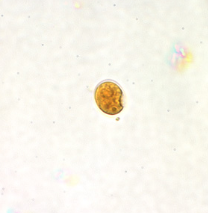

Professor: Dr. Glena Fe A. Yapchulay-Alcabasa

BLASTOCYSTIS HOMINIS VACUOLAR FORM